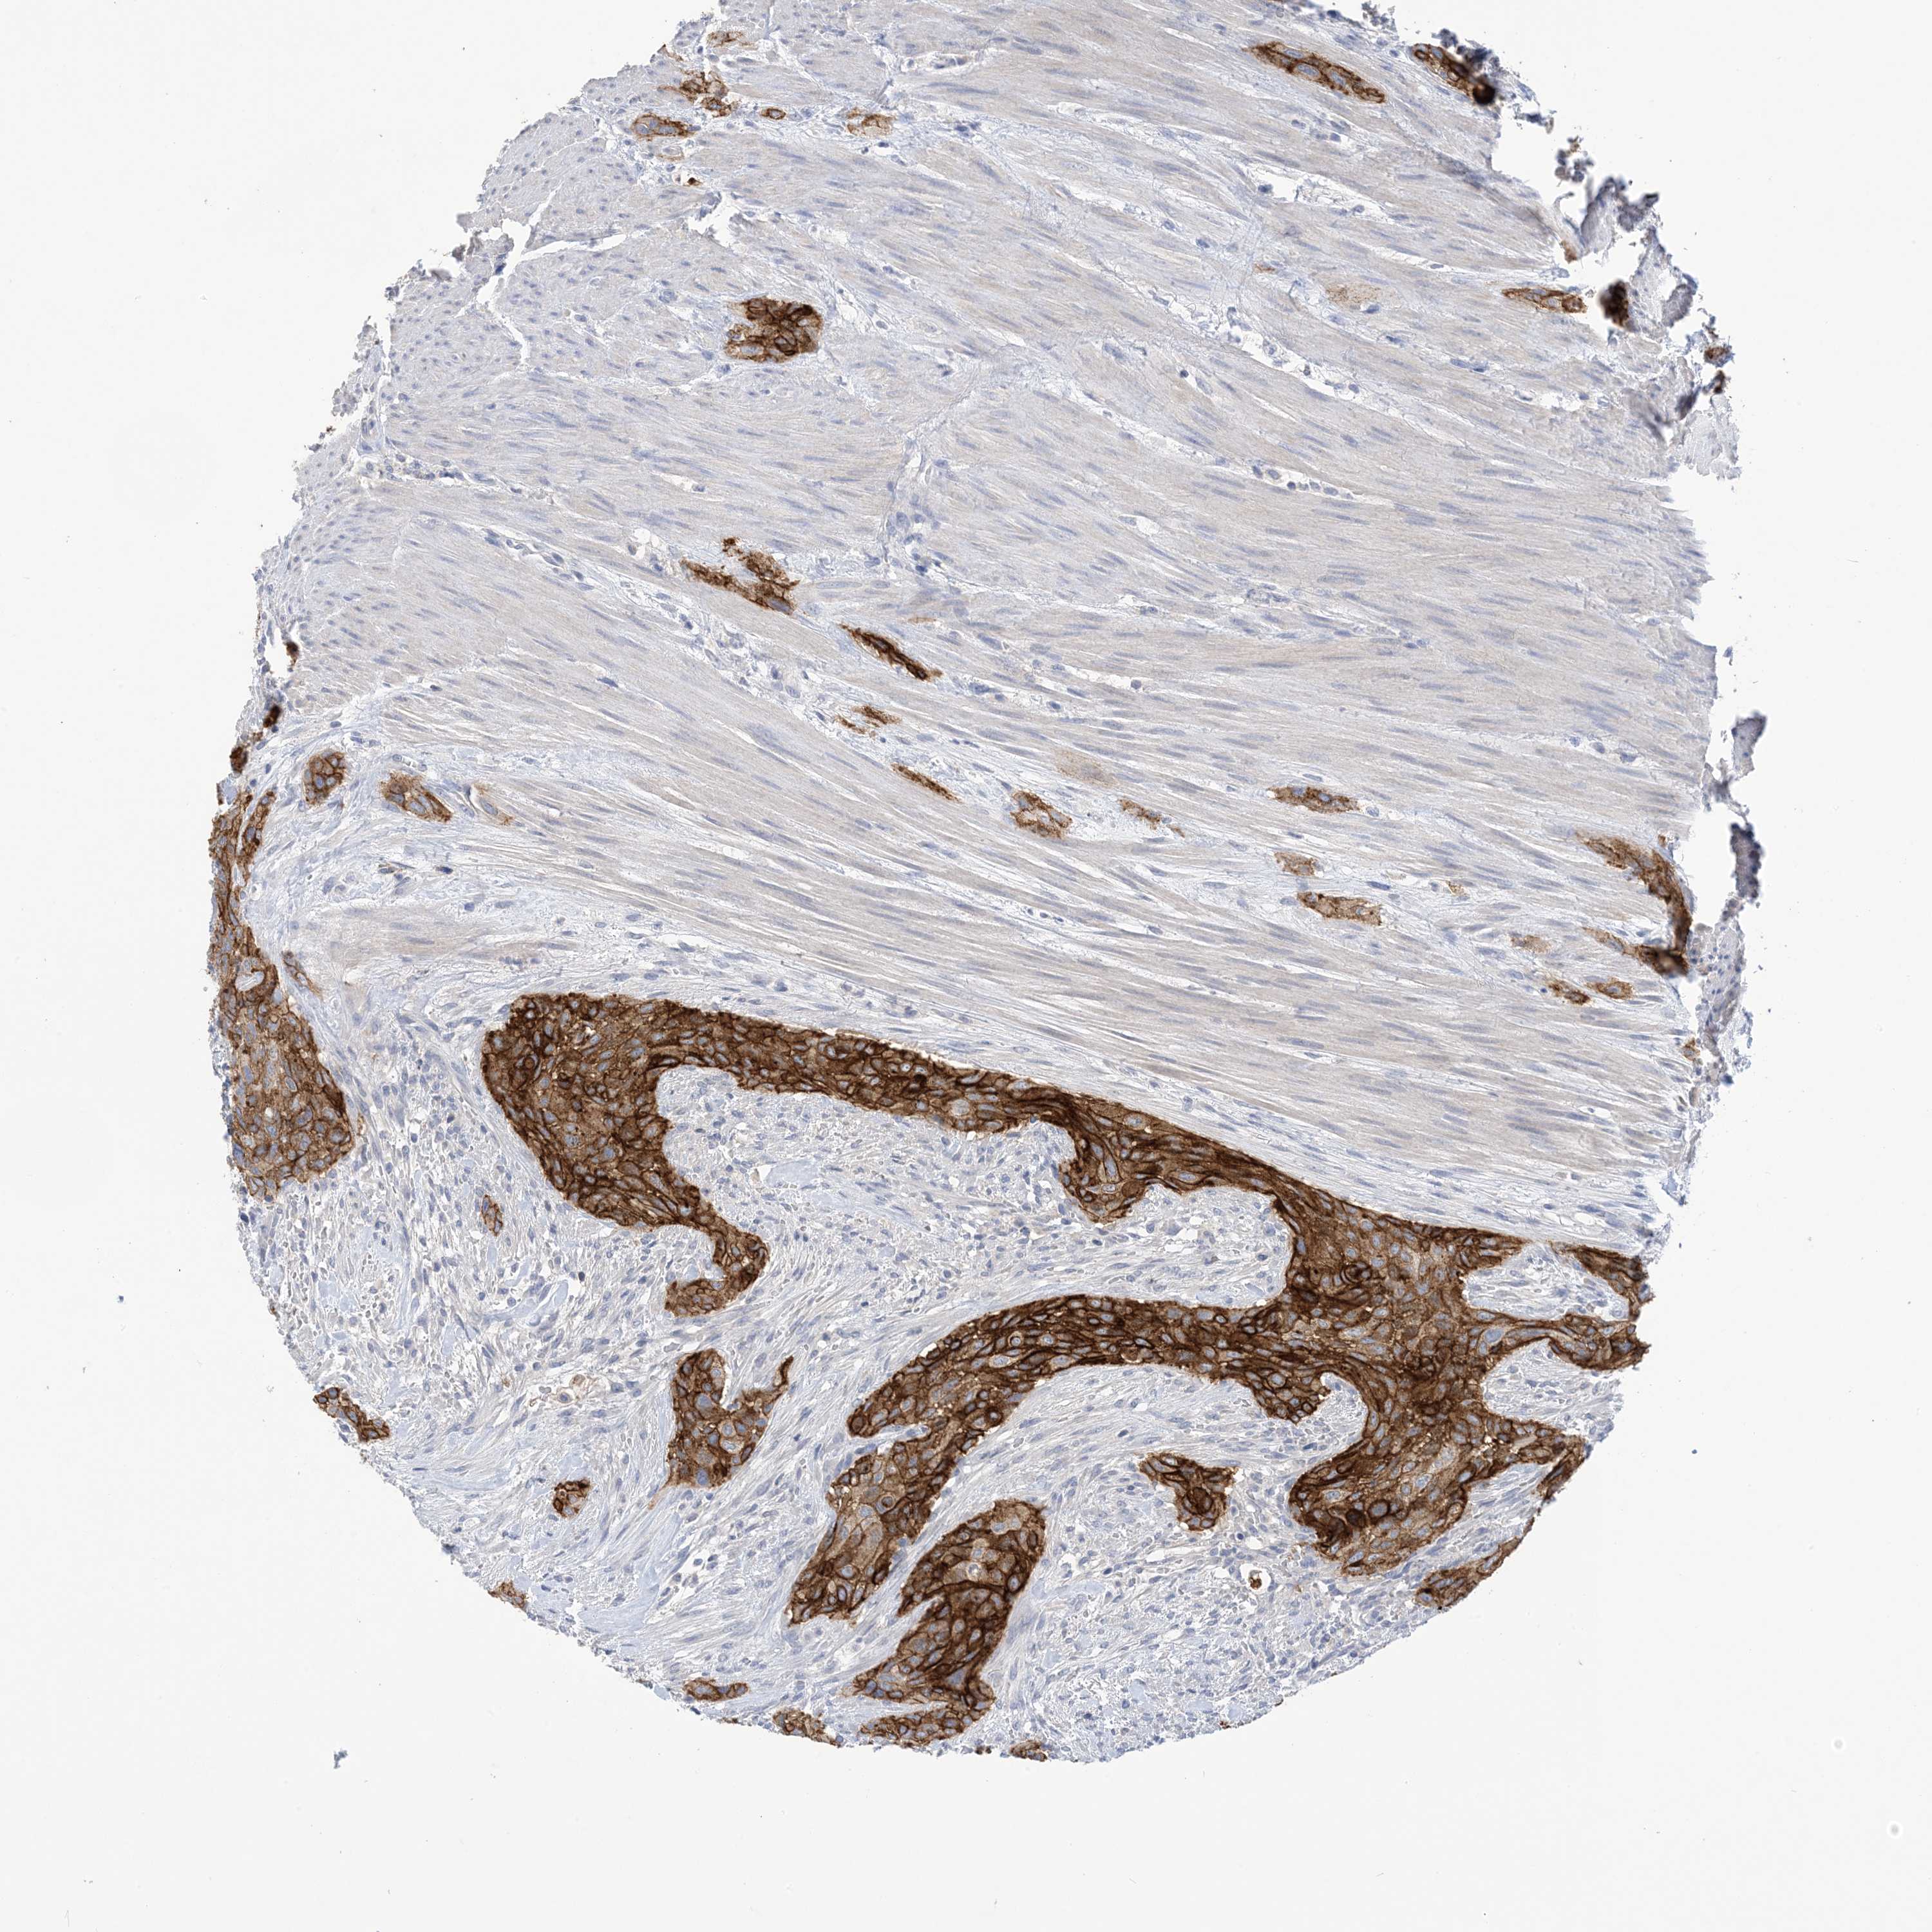

UROTHELIAL CANCER - Protein expressioni

A mouse-over function shows sample information and annotation data. Click on an image to view it in a full screen mode. Samples can be filtered based on level of antibody staining by selecting one or several of the following categories: high, medium, low and not detected. The assay and annotation is described here.

Antibody stainingi

Antibody staining in the annotated cell types in the current human tissue is reported as not detected, low, medium, or high, based on conventional immunohistochemistry profiling in selected tissues. This score is based on the combination of the staining intensity and fraction of stained cells.

Each image is clickable and will lead to virtual microscopy that enables deeper exploration of all samples and also displays staining intensity scores, fraction scores and subcellular localization as well as patient and tissue information for each sample.

Antibody HPA049265

Antibody CAB037328

Urothelial carcinoma, High grade

Urothelial carcinoma, Low grade

Urothelial carcinoma, NOS